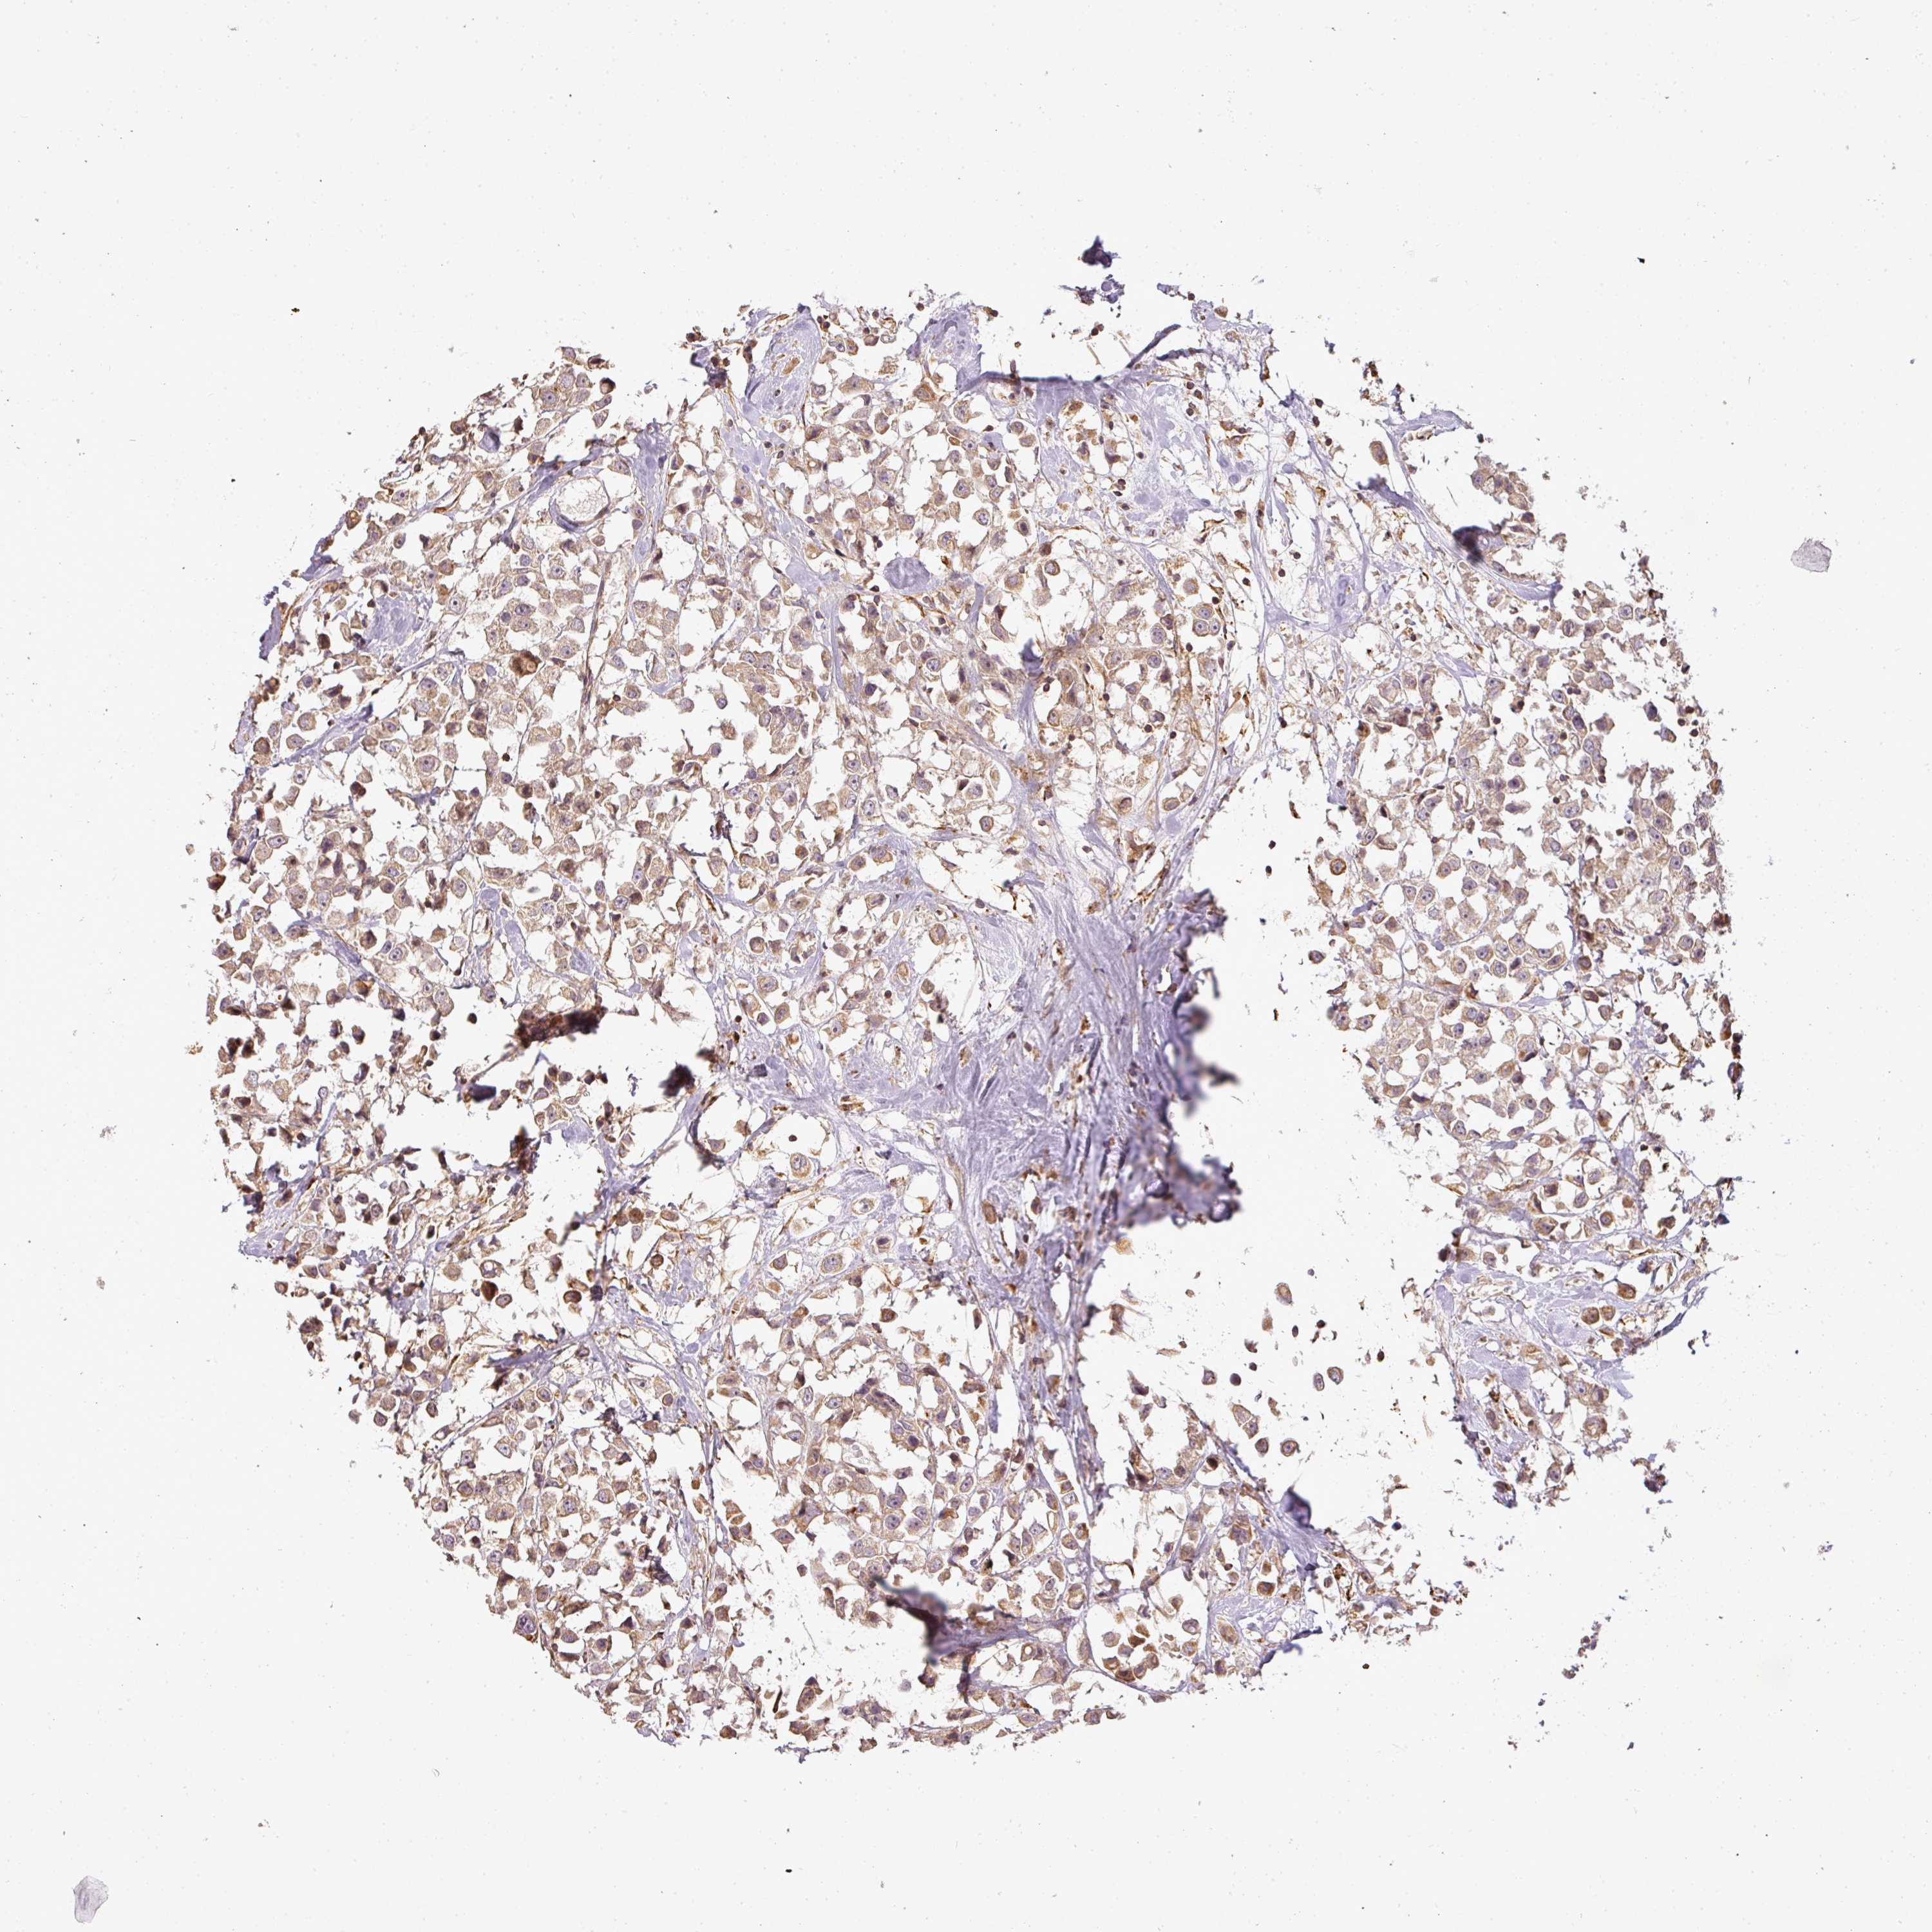

CANCER BREAST CANCER Show tissue menu

BRCA TCGA BRCA VALIDATION PROTEIN EXPRESSION